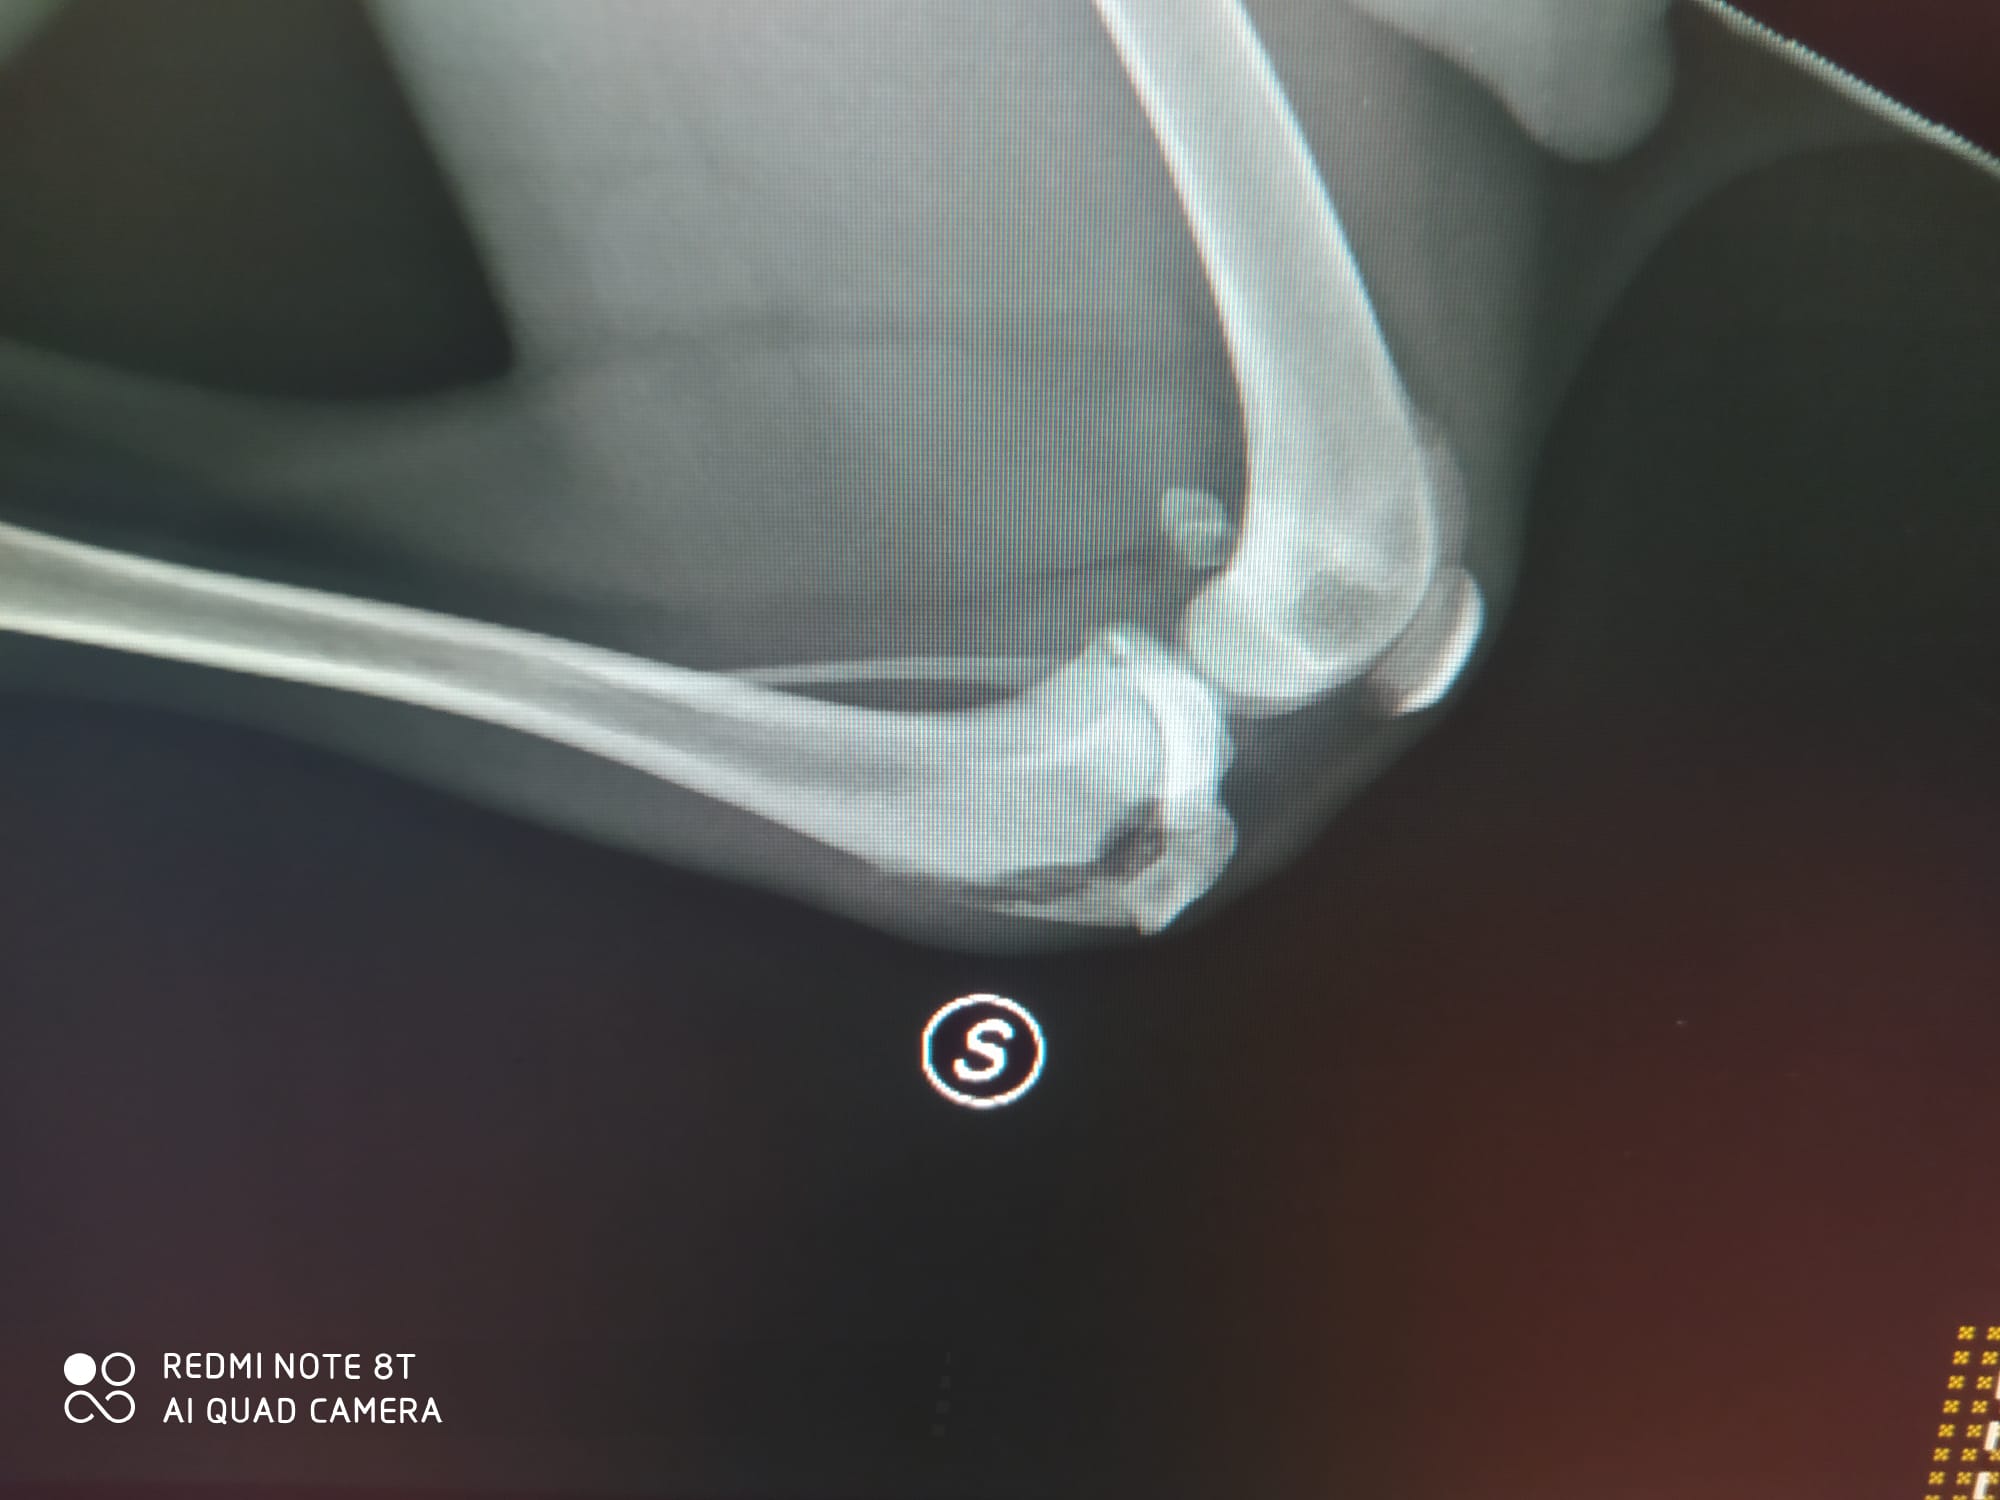

Zitat von Redaktion neu am 20. Februar 2024, 18:05 UhrBill wurde nun operiert, es geht ihm den Umständen entsprechend gut. Beide Hinterbeine mussten operiert werden.

Er muss jetzt ca. 4 Wochen absolute Ruhe halten, was sich natürlich für so einen

jungen Hund schwierig ist. Er ist in einer kostenpflichtigen Pension untergebracht.Daher bitten wir weiter dringend um Spenden damit die Behandlungskosten gedeckt werden können.

Bill wurde nun operiert, es geht ihm den Umständen entsprechend gut. Beide Hinterbeine mussten operiert werden.

jungen Hund schwierig ist. Er ist in einer kostenpflichtigen Pension untergebracht.